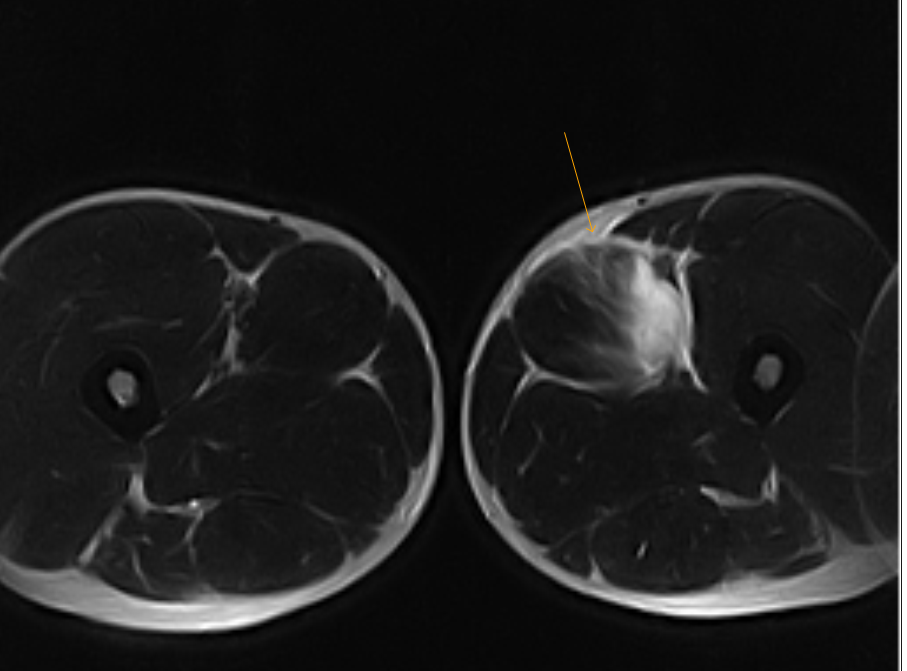

MRI images of hydatid cyst within adductor muscles containing daughter

T2 MRI scan of the right thigh showing 4.5 cm mass (red arrows) within Adductor Muscle Edema Mri muscle edema is seen secondary to multiple etiologies including trauma, infectious and inflammatory processes, autoimmune. magnetic resonance (mr) imaging is well suited for the direct and detailed assessment of soft tissue, including. (a) axial t 2 weighted mr image shows the enlarged adductor and biceps femoris. the presence of skeletal muscle edema (increased high t2/stir signal). Adductor Muscle Edema Mri.